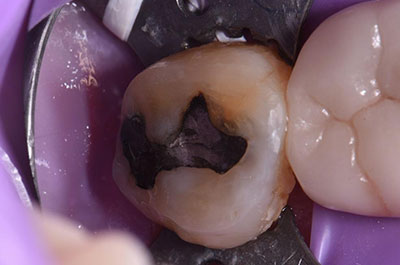

Classic case of a long standing fractured restoration on tooth 3.7 (#18) and overerupted 2.7 (#15). A crown preparation on heavily restored 3.7 with limited interocclusal space required heavy occlusal reduction paired with enameloplasty cum dentinoplasty on 2.7 resulting in tactile hypersensitivity. The amalgam restoration on 2.7 was planned for replacement anyways. The goal was to attempt to not need to complete elective endodontics on 2.7 if it could be avoided. A monolithic Zenostar zirconia crown with areas of occlusal minimal thicknesses of 0.5mm (ideally this should always be 1.0mm as a minimum) was fabricated and the opposing occlusion ordered to be reduced further by the laboratory. The Zr crown was prepared for “bonding” via the APC approach (Markus Blatz) and cemented using Panavia SA Plus via a total etch technique (Photobond DC – Kuraray). The 2.7 was restored after removal of the amalgam and reduction of areas of dentin exposure further using a layered approach with Voco Grandio SO with relatively flat occlusal anatomy. All in all, the pulpal vitality has been preserved in 2.7 whilst hopefully allowing a long service life of the Zr crown on 3.7.